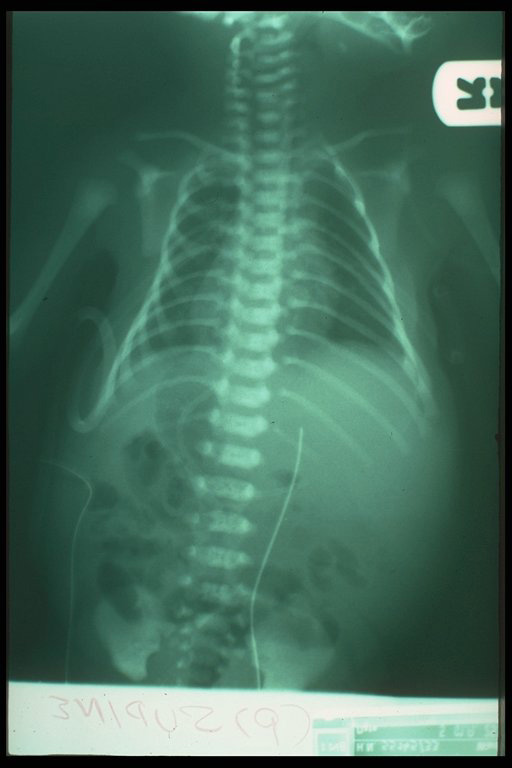

Three days after intercostal drainage of bilateral chylothorax. Both lungs expanded well. Generalized edema was still noted from the film.